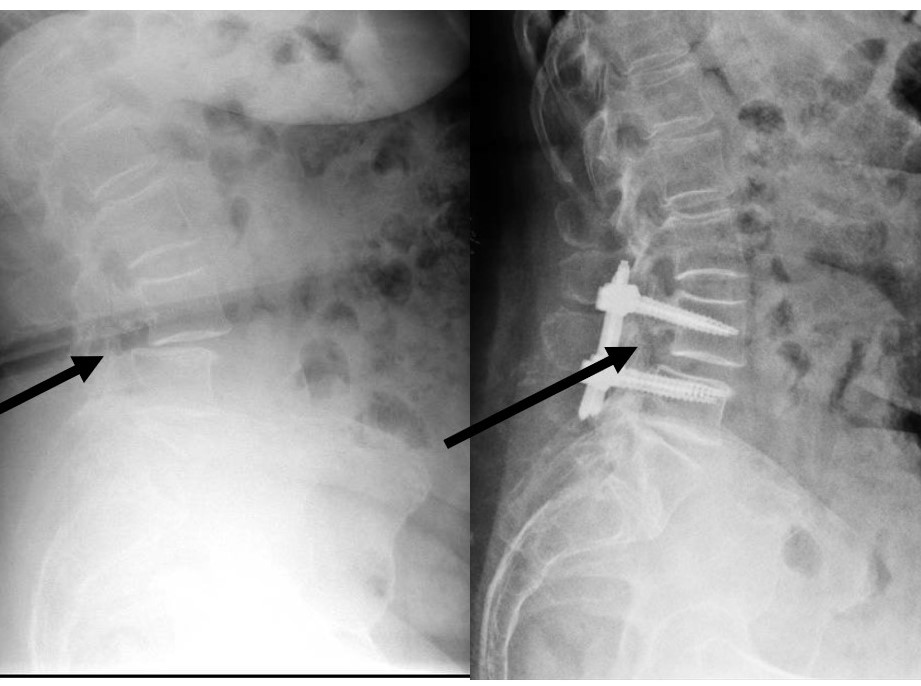

–Fracturas vertebrales: Frecuentes sobre todo en la columna dorso-lumbar, pueden aparecer como consecuencia de mecanismos muy diversos; desde grandes traumatismos, en cuyo caso su tratamiento puede estar condicionado por la presencia de otras lesiones, o bien tras traumatismos banales o incluso de forma espontánea, sin traumatismo alguno. Estos últimos casos definen las «fracturas patológicas» en las que es preciso buscar una causa subyacente estructural o sistémica que haya provocado el debilitamiento óseo. Esta situación es especialmente frecuente en mujeres tras la menopausia debido al desarrollo de osteoporosis. Estos casos precisan iniciar un tratamiento para compensar la desmineralizacón ósea. El tratamiento de las fracturas depende fundamentalmente del grado de deformidad asociado, la afectación de ligamentos (ambos aspectos definen la presencia o no de inestabilidad) y el que exista o no una lesión neurológica. En caso de fracturas estables sin déficit neurológico se emplea una ortesis mientras que en presencia de inestabilidad o afectación neurológica debe valorarse la cirugía.

- Estabilizacion vertebral percutánea: Es el procedimiento empleado para tratar los casos que precisan fijar dos o más vértebras debido a la presencia de inestabilidad o fracturas. Gracias al empleo de imagen intraoperatoria y a los sistemas de fijación de alta precisión es posible llevar a cabo esta técnica de forma mínimanente invasiva mediante pequeñas incisiones de apenas 2 cm a través de las cuales se introducen tornillos al pedículo de la vértebra así como barras laterales. El respeto por la musculatura paraespinal, clave para el resultado final, es por tanto máximo gracias a esta técnica. La ejecución de la misma gracias al aprovechamiento de aspectos como la colocación bicortical de los implantes y las técnicas de reduccion percutánea de la deformidad permiten un restablecimiento de la anatomía en una amplia proporción de casos con un riesgo mínimo.